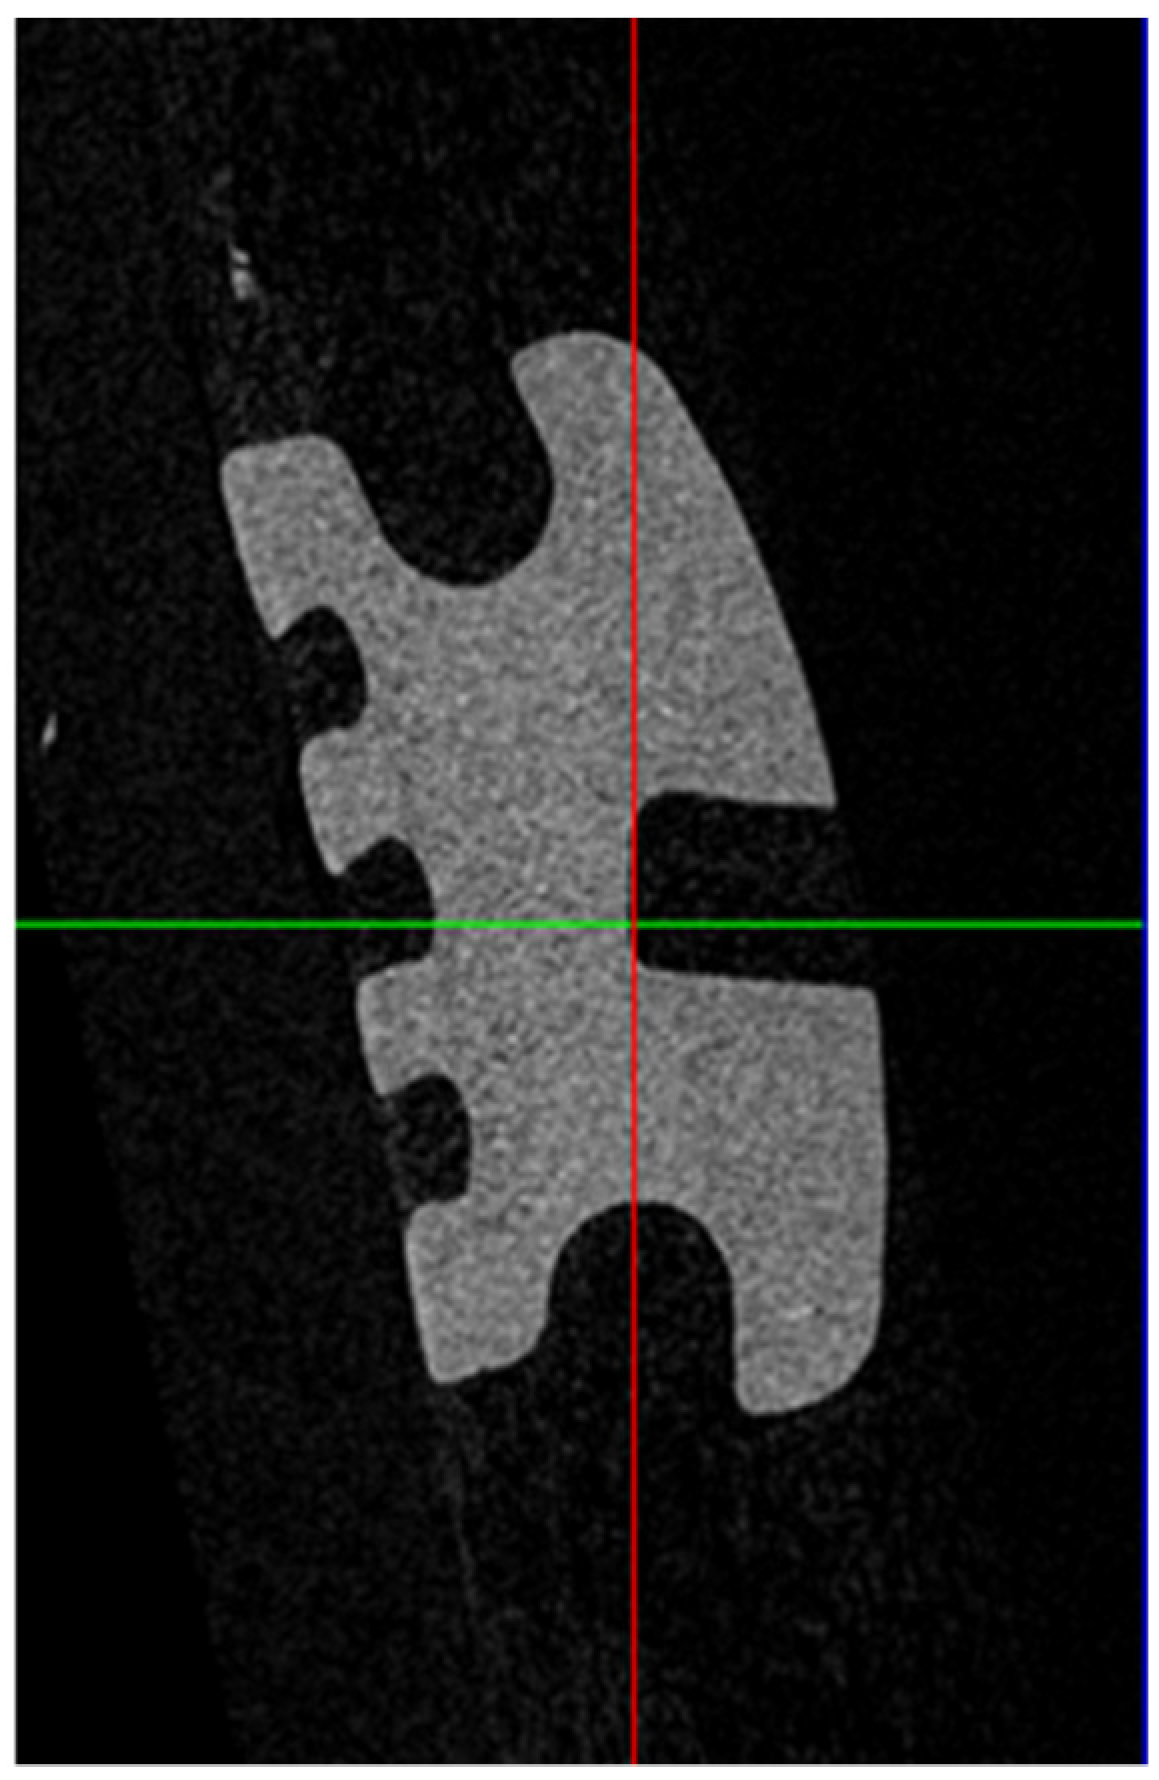

The resultant 4000 voxel three-dimensional images were manipulated using dedicated software (DataViewer; Bruker microCT, Kontich, Belgium) to standardize the orientation of the image. This was achieved by aligning the base of the bracket slot so that it was parallel to the X–Y plane. Two-dimensional images were obtained in the Y–Z plane at the middle of the distal wing slot on each bracket for analysis. They were then processed using dedicated software (CTAn; Bruker microCT, Kontich, Belgium), where images were binarized by thresholding, and, then, saved for further analysis. The images were exported into image-analysis software (Image J; WS Rasband, US National Institutes of Health, MA, USA), so that measurements could be taken (Figure 3).

Figure 3.

Micro-computed tomography (micro-CT) image of a ceramic bracket.